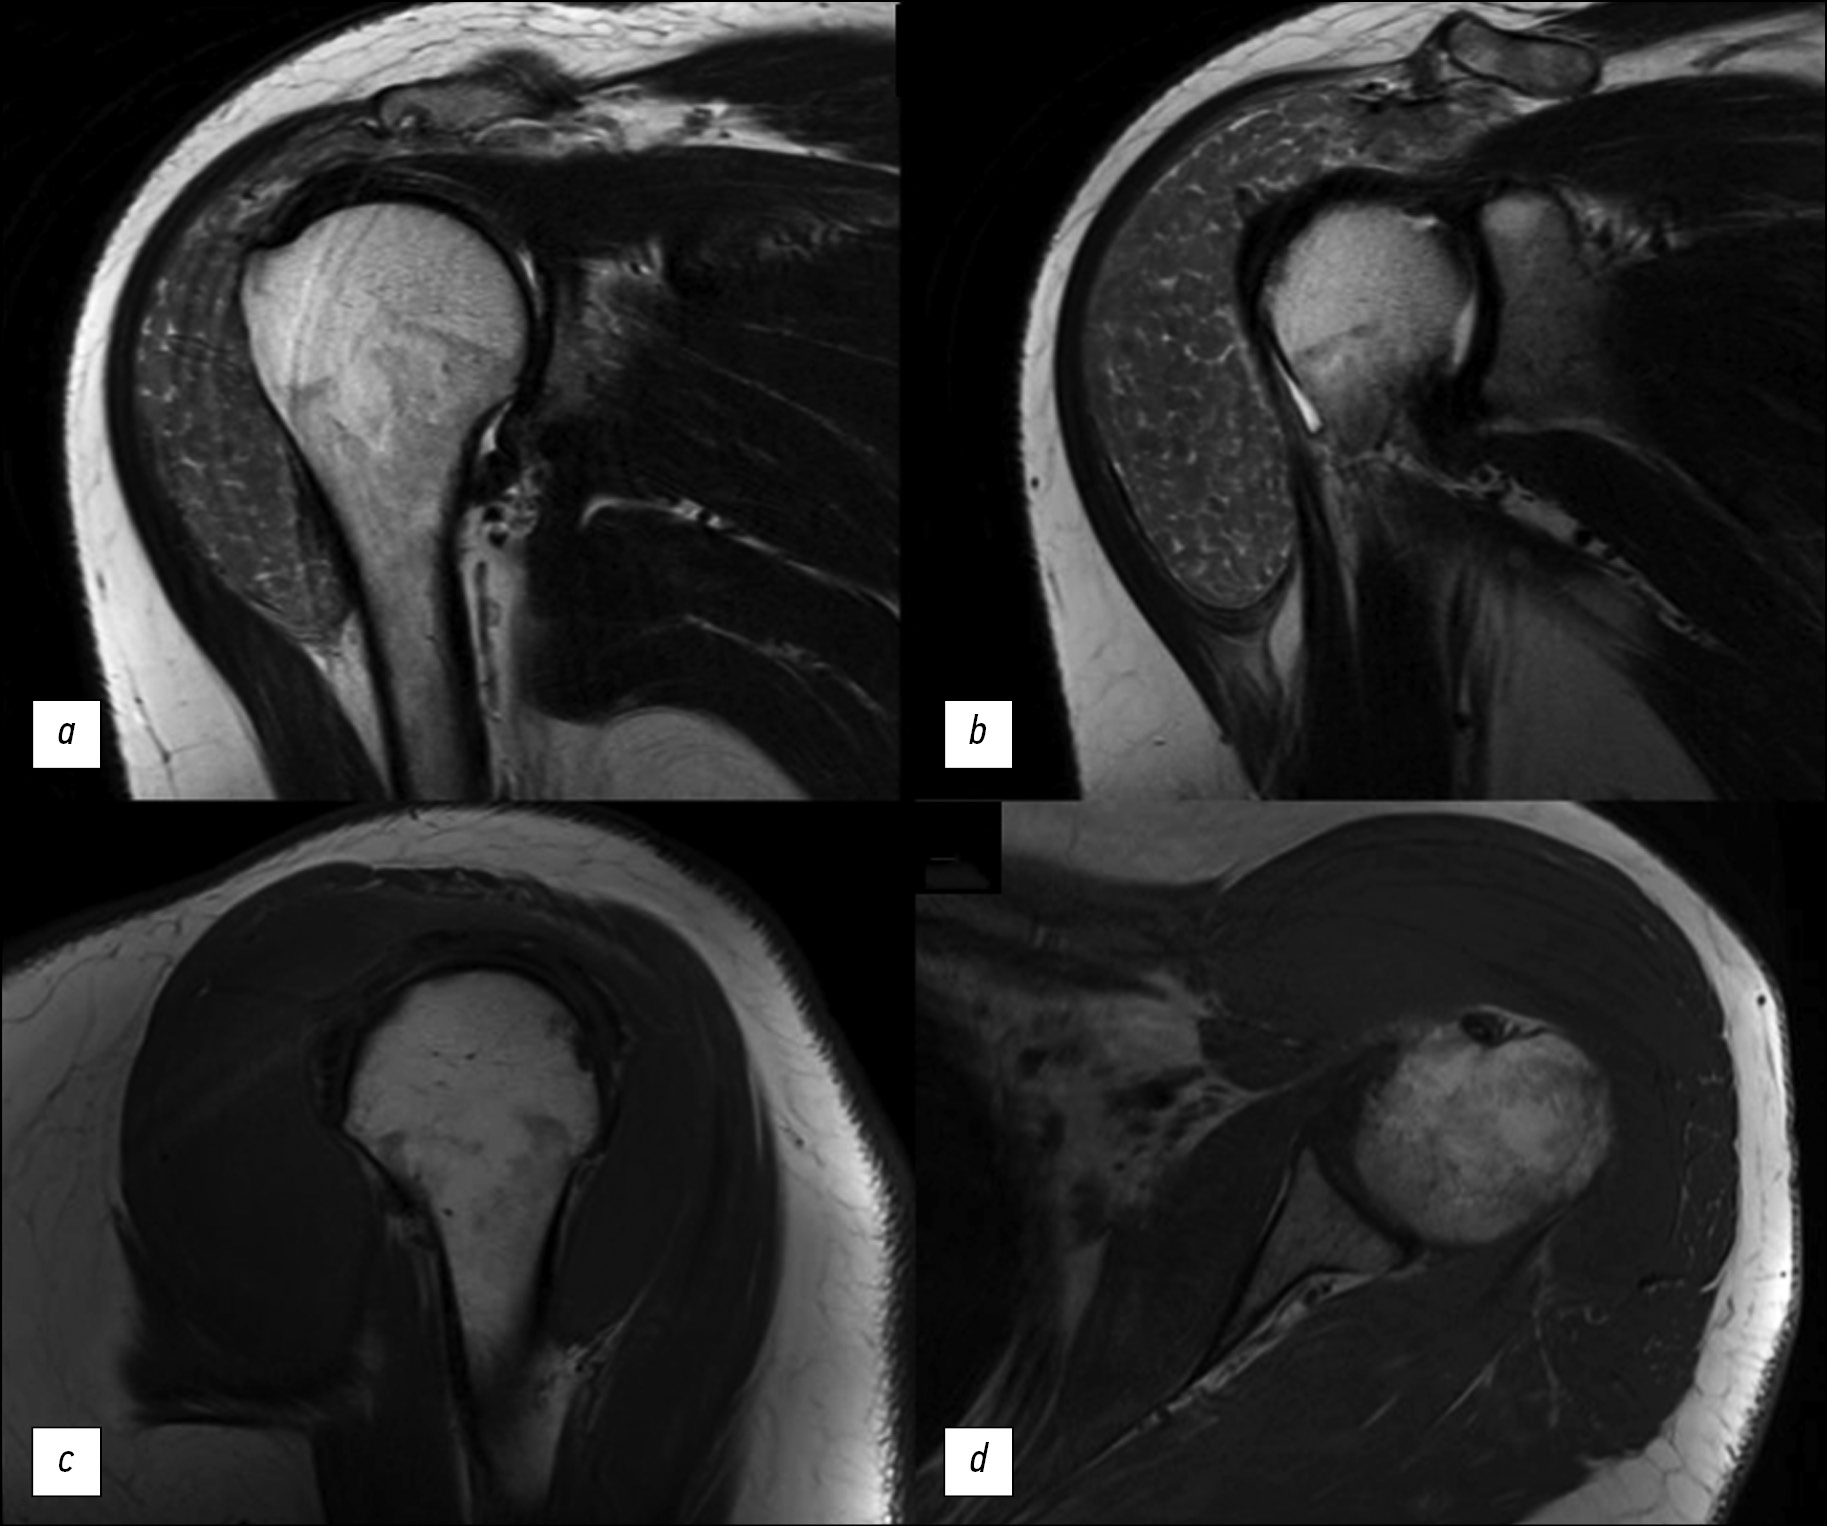

Under the deltoid, inside the subacromial bursa and subdeltoid bursa enlarged to the size of 7.7 × 2.5 × 5 cm, T2-weighted imaging (WI) showed multiple similarly shaped oval structures measuring 2–3 mm to 8–10 mm in diameter with an intermediate signal intensity, separated by areas of increased signal intensity (in T2-WI). In T1-WI, these structures demonstrated homogeneous intermediate signal intensity (Figs. 1 and 2). Agglomerations of small inclusions resembled space-occupying masses in the joint cavity.

Fig. 1. Magnetic resonance imaging of the left shoulder joint: a, b — T2-weighted images, coronal sections; c — T1-weighted image, sagittal section; d — T1-weighted image, transverse section.

In MRI, rice bodies are visualized as multiple small, similarly shaped, rounded structures. In T1-WI, they are isointense or hypointense; in T2-WI, they are hypointense. The T2-WI pattern in the described case consisted of densely agglomerated inclusions, which were hyperintense compared with the muscle tissue, which is typical in RA. As demonstrated in the case presented, MRI is superior to CT in identifying rice bodies.